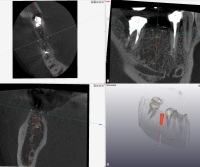

■歯科用CT撮影

CAD/CAM冠

従来までの歯科レントゲン装置では一方向からの平面画像しか得られませんでしたが、歯科用CTでは歯や骨を3次元的な立体画像で撮影できます。また、歯の内部や骨の内部まで360°あらゆる方向から立体的に見ることができますので、より正確な診断や治療計画を立てることが可能になります。とりわけ有用なのは、埋伏歯根管治療歯周病インプラント顎関節症などになります。(一般的な虫歯診断にCTは向きません。)

「他院でレントゲンを撮ったが原因が分からず診断がつかなかった」

「根管治療を何ヶ月も続けているが一向に治らない」

「抜くしかないと言われたが本当にそうなのか精密検査したい」など、

歯科用CT撮影が診断に大いに役立つケースは多くあります。ご希望の方はご相談ください。(保険外1撮影5,000円) 尚、一部保険が適用できる場合もあります。

CTと聞くと放射線被曝量をご心配される方も多いと思いますが、歯科用CTは医科用CTとはX線の照射方式が異なるため、被曝量は非常に少なくなっています。被曝量は医科用CTによる胸部撮影の約70分の1、胃の単純X線撮影の約6分の1、飛行機による東京~ニューヨーク間の往復(高高度による宇宙放射線被爆)よりも少ない(約2分の1)という参考データがあります。